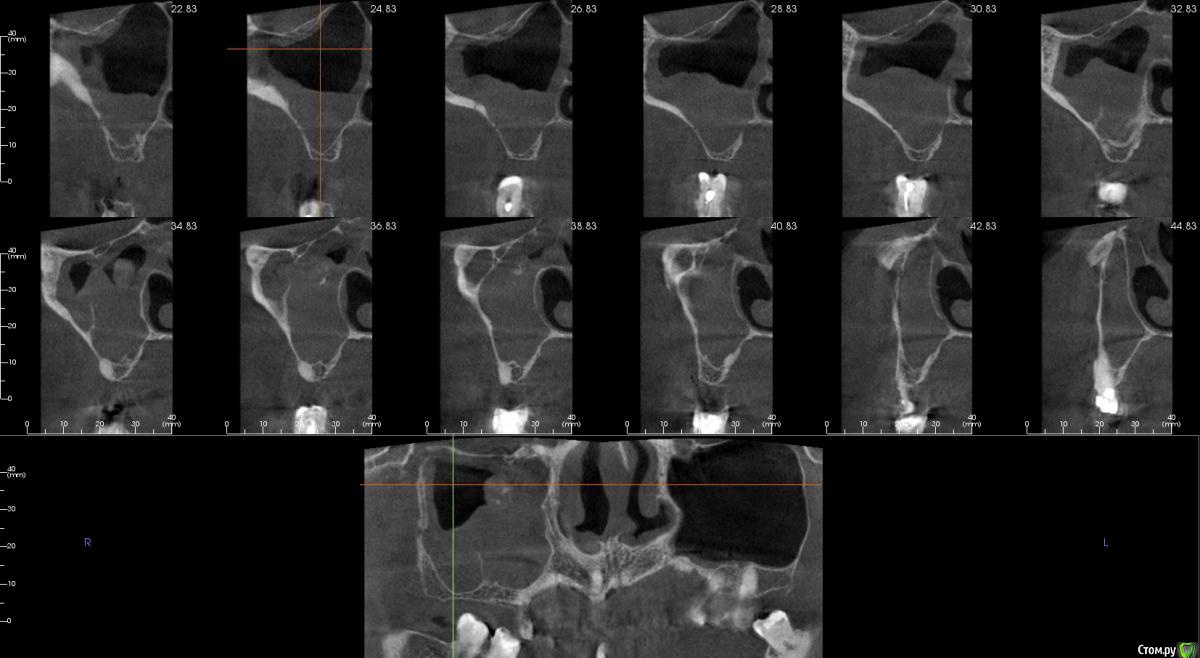

Irouil Опубликовано 16 апреля, 2018 Поделиться Опубликовано 16 апреля, 2018 Имхо - нет. ЛОР КТ смотрел вообще? Тут может быть что угодно, от уровня жидкости до инвертированной папиломы. Ссылка на комментарий

kamranchick Опубликовано 16 апреля, 2018 Автор Поделиться Опубликовано 16 апреля, 2018 Смотрел, и такое заключение дал. вот меня и смутило, в верхней трети около соустя вообще вкрапления какие то есть )) Ссылка на комментарий

Irouil Опубликовано 16 апреля, 2018 Поделиться Опубликовано 16 апреля, 2018 Смотрел, и такое заключение дал. вот меня и смутило, в верхней трети около соустя вообще вкрапления какие то есть ))Больше всего похоже на грибковое тело, и вкрапления эти намекают, и контуры затенения. Пунктировать не стал ЛОР это? 1 Ссылка на комментарий

kamranchick Опубликовано 16 апреля, 2018 Автор Поделиться Опубликовано 16 апреля, 2018 Больше всего похоже на грибковое тело, и вкрапления эти намекают, и контуры затенения. Пунктировать не стал ЛОР этоОтправил для санации, он написал вот это только( что ретенционная, но потом я внимательно начал крутить туда сюда и вот засомневался Ссылка на комментарий

Irouil Опубликовано 16 апреля, 2018 Поделиться Опубликовано 16 апреля, 2018 По большому счету; какая разница то? Вы же пациентку ради синус лифта (насколько я понимаю) отправляли, в таких условиях его не сделать. Там даже если соустье толщиною с пенис Трампа будет, все равно его ткани+отек перекроют после синуса. Так или иначе пазуху надо оперировать, только если ЛОР не считает что ретенционная киста - одонтогенная и пройдет при санации первичного очага) Ссылка на комментарий